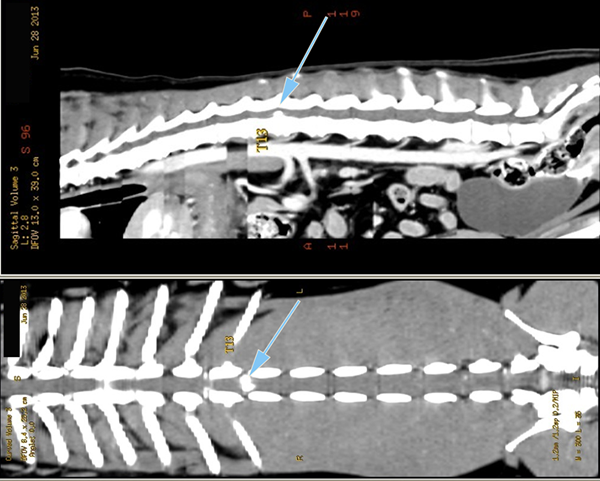

Le scanner est actuellement l'examen de choix pour le diagnostic des hernies discales chez les carnivores domestiques et d'une façon générale pour l'exploration des pathologies du rachis. Ses capacités de dessuperposition des structures anatomiques et sa meilleure résolution spatiale lui permettent, avec les machines de dernière génération, de supplanter définitivement les examens radiologiques sous contraste.

Le scanner permet à la fois une meilleure approche de l'étage de la lésion, mais aussi une meilleure latéralisation de celle-ci, ce qui est capital en cas de geste chirurgical. Il permet aussi, en cas de hernies multiples (ce qui est fréquent dans certaines races comme le Bouledogue français) d'avoir une approche lésionnelle permettant, au travers de critères objectifs, de faire un tri entre les hernies pour isoler celle responsable des symptômes nerveux.

L'examen tomodensitométrie du rachis se fait avant et après injection de produit de contraste iodé pour rehausser les lésions. Dans certains cas extrêmes, et au demeurant rarissimes, une injection complémentaire de produit de contraste dans l'espace sous arachnoïdien peut être nécessaire, l'examen réalisé alors se nomme un myéloscanner. Cet examen peut s'avérer très utile, notamment pour le diagnostic de certaines affections rares des méninges nommées kystes arachnoïdiens, présentes en particulier chez le Rottweiler, et dont le diagnostic constitue une des limites du scanner avec le syndrome de Chiari.

Scanner d'une Hernie discale T13L1 extrusive chez un chien reformatages sagittal et coronale